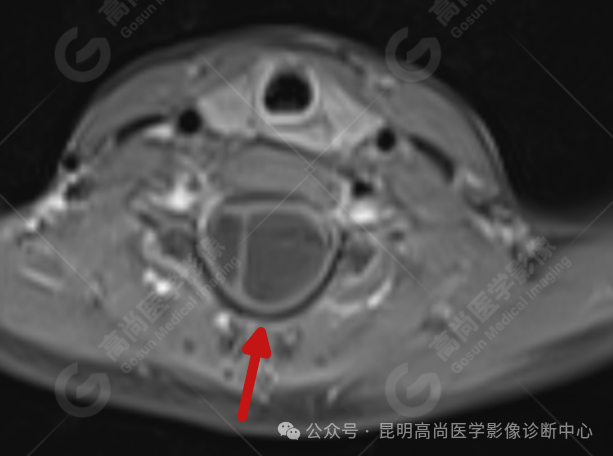

患者女,5 岁,出生时发现颈部包块,大小 3 cm×3 cm,5 年来无变化,拟行手术治疗,要求增强核磁协诊,否认体内金属物,无过敏史。

影像表现

颈 3-5 层面颈后部软组织不规则片状异常信号影,脊膜膨出可能;颈 3、4 棘突局部显示不清;颈胸髓内(约颈 3-胸 9 椎体水平)异常信号影,考虑囊肿并局部颈髓空洞可能,肿瘤或其他待排;请结合临床及相关检查。